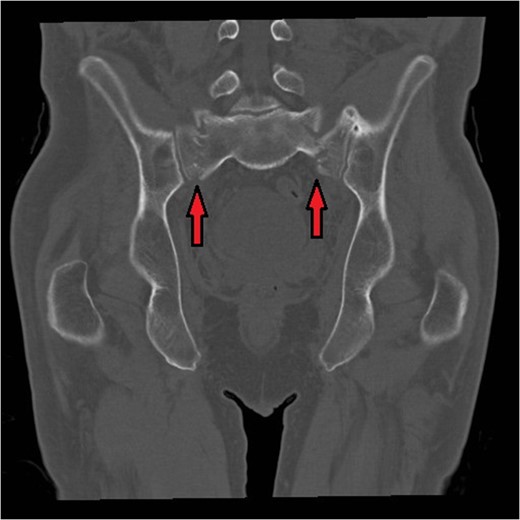

Bilateral sacral fractures (in line with arrows) are clearly visualized on the coronal reformat of CT pelvis.